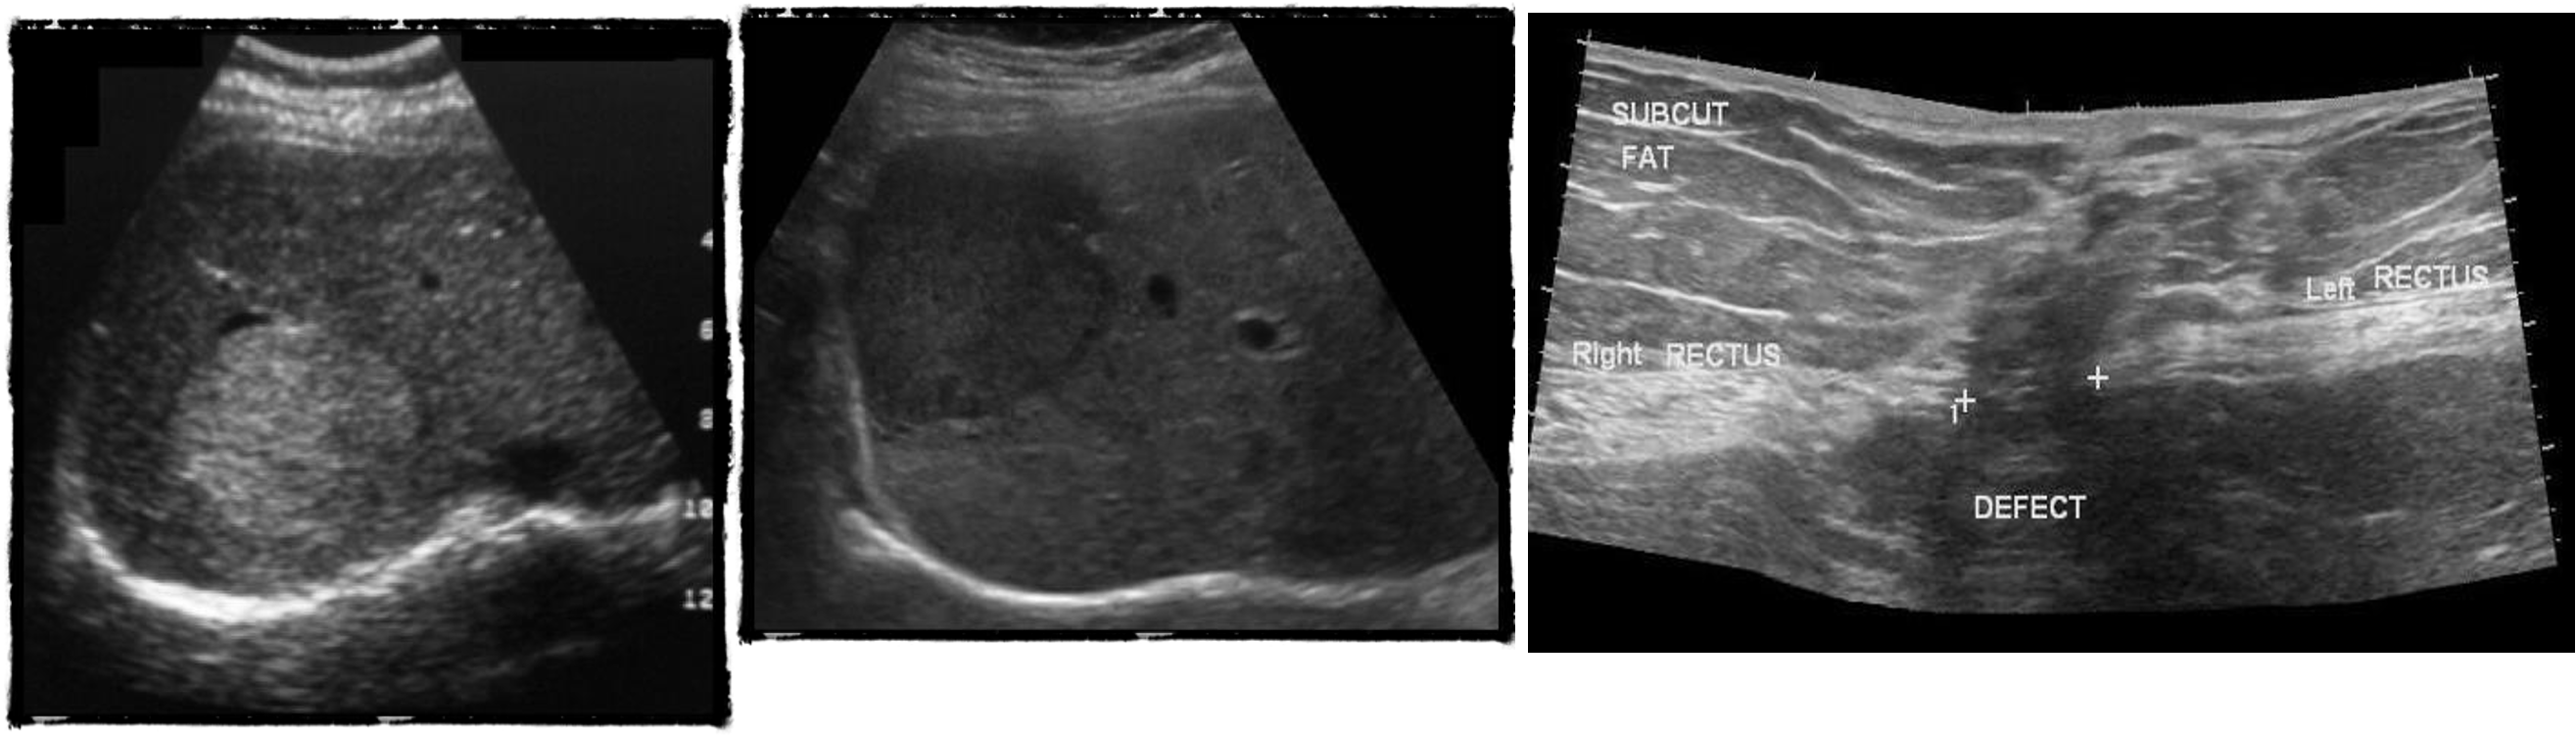

U/S

- chronic chole

- hyperechoic - post acoustic shadow…

- acute cholecystitis

- acute edematous thick gallbladder

- stone tumour

hydiatted

HCC